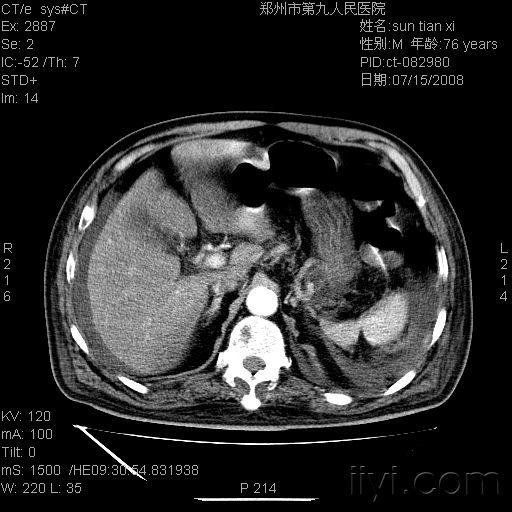

请教ct对肝门静脉血栓敏感吗